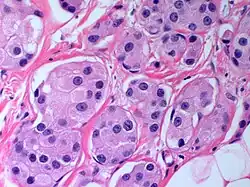

The microscopic histopathology of PACB tumors prepared with hematoxylin and eosin staining shows that >90% of the tumors consist of apocrine gland-like tissue. The lesions must also show that tumor cells have broken through their ducts of origin to invade adjacent tissue in at least one area. Most of the tumor cells (termed type A cells[15]) typically appear somewhat more irregular than normal apocrine gland cells. They have abundant eosinophilic (i.e. pink due to the uptake of the eosin dye) cytoplasm which contain numerous granules[11] and large mitochondria.[15] Their nuclei are large, variably sized and shaped, have multiple nucleoli (which are eosinophilic[11] and may be distinctively large in size[14]), and are surrounded by highly visible nuclear membranes. The cells are arranged into solid sheets, nests, papillae, and/or cords (see Figs. 1 and 2).[11] The tumor cells' cytoplasmic granules test positive when treated with the PAS diastase stain.[16] Binucleated cells, i.e. cells with two nuclei, are common.[10] Less commonly, type B apocrine cells are present; these cells have a more foamy and vacuolated cytoplasm (i.e. containing multiple vacuoles) than type A cells[15] and often resemble foamy histiocytes or sebaceous gland cells.[17] The tumor cells have low to moderate rates of proliferation based on their Ki-67 protein levels.[7] PACB tissues may have localized areas that contain mucin-like secretions within their luminal ducts,[10] localized areas of necrosis (i.e. foci containing dead or dying cells), and/or microcalcifications spotted throughout the apocrine tissue.[11] The stroma (i.e. connective tissue between the sheets, nests, papilla and cords of cells) typically contains non-malignant, infiltrating lymphocytes (see Fig. 3). In an examination of 41 PABC tumors, 33 (80.5%) had <50% of their stroma tissues infiltrated with these cells while 8 (19.5%) had ≥50% of their stroma tissues infiltrated with them. Tumors with ≥50% of their stroma infiltrated with lymphocytes tended to have carcinoma cells that had high rates of proliferation.[11] Metastatic and recurrent PACB tumors have a histopathology similar to their original primary tumors.[14]